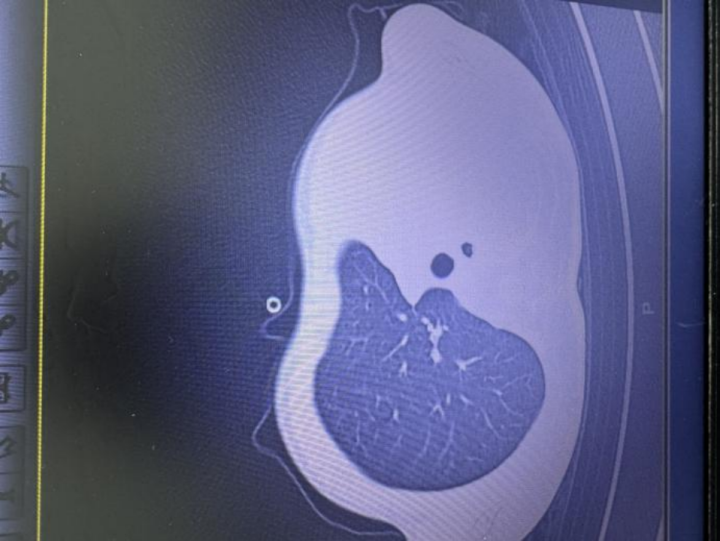

急诊检查结果让医护人员瞬间紧张:验血显示炎症指标大幅上升,胸片更发现左侧肺叶几乎“不工作了,影像学中变成大片白色,即通常所说的“白肺”,钙v交流群意味着肺功能严重受损,孩子已经缺氧,随时有窒息危险。

图:影像显示肺白了一半